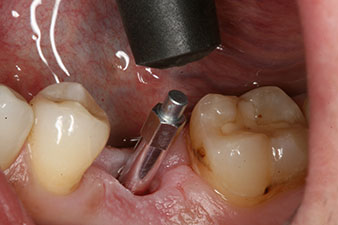

SmartPeg

Abb. 4: Eingeschraubter SmartPeg Messpfosten für die Bestimmung des Implantatstabilitäts-Quotienten mit dem integrierten W&H Osstell ISQ Modul.

Das Drehmoment beim maschinellen Einbringen war 43 Ncm. Zusätzlich wurde, nach Einschrauben eines speziellen, auf das Implantatsystem abgestimmten Mess-Pfostens (SmartPeg), der ISQ-Wert mit der Sonde des W&H Osstell ISQ Modul bestimmt.